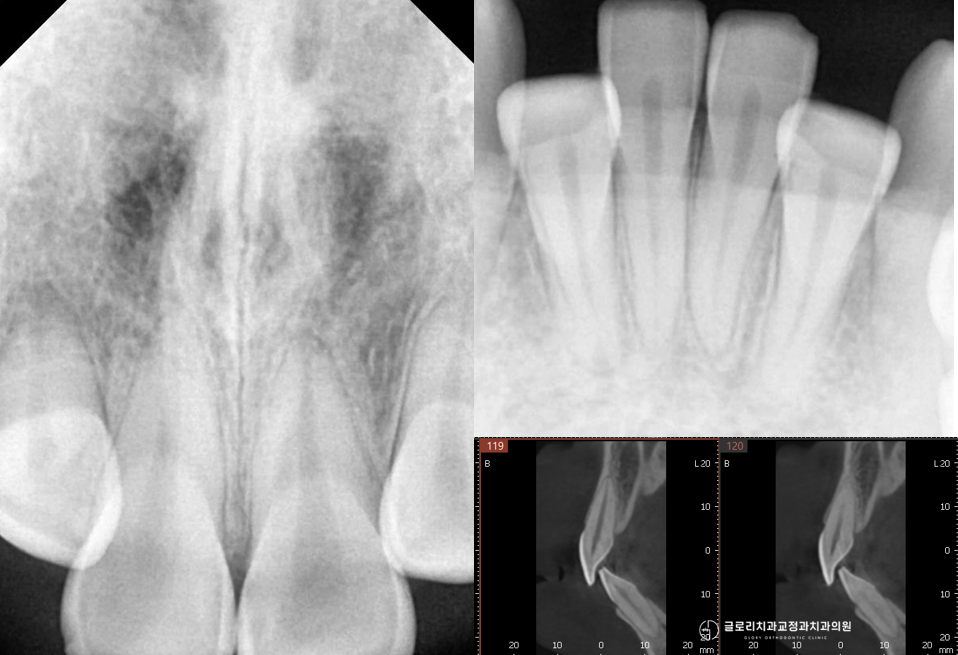

이때 정밀 검사를 통해 발치 필요 여부를 신중하게 판단합니다.

또한 치아 뿌리가 잇몸뼈 바깥으로 밀려나는 치근 노출 위험도 고려해야 합니다.

무리하게 비발치 교정을 고집하면 교정 후 안정성이 떨어지거나 예상치 못한 부작용이 생길 수 있습니다.